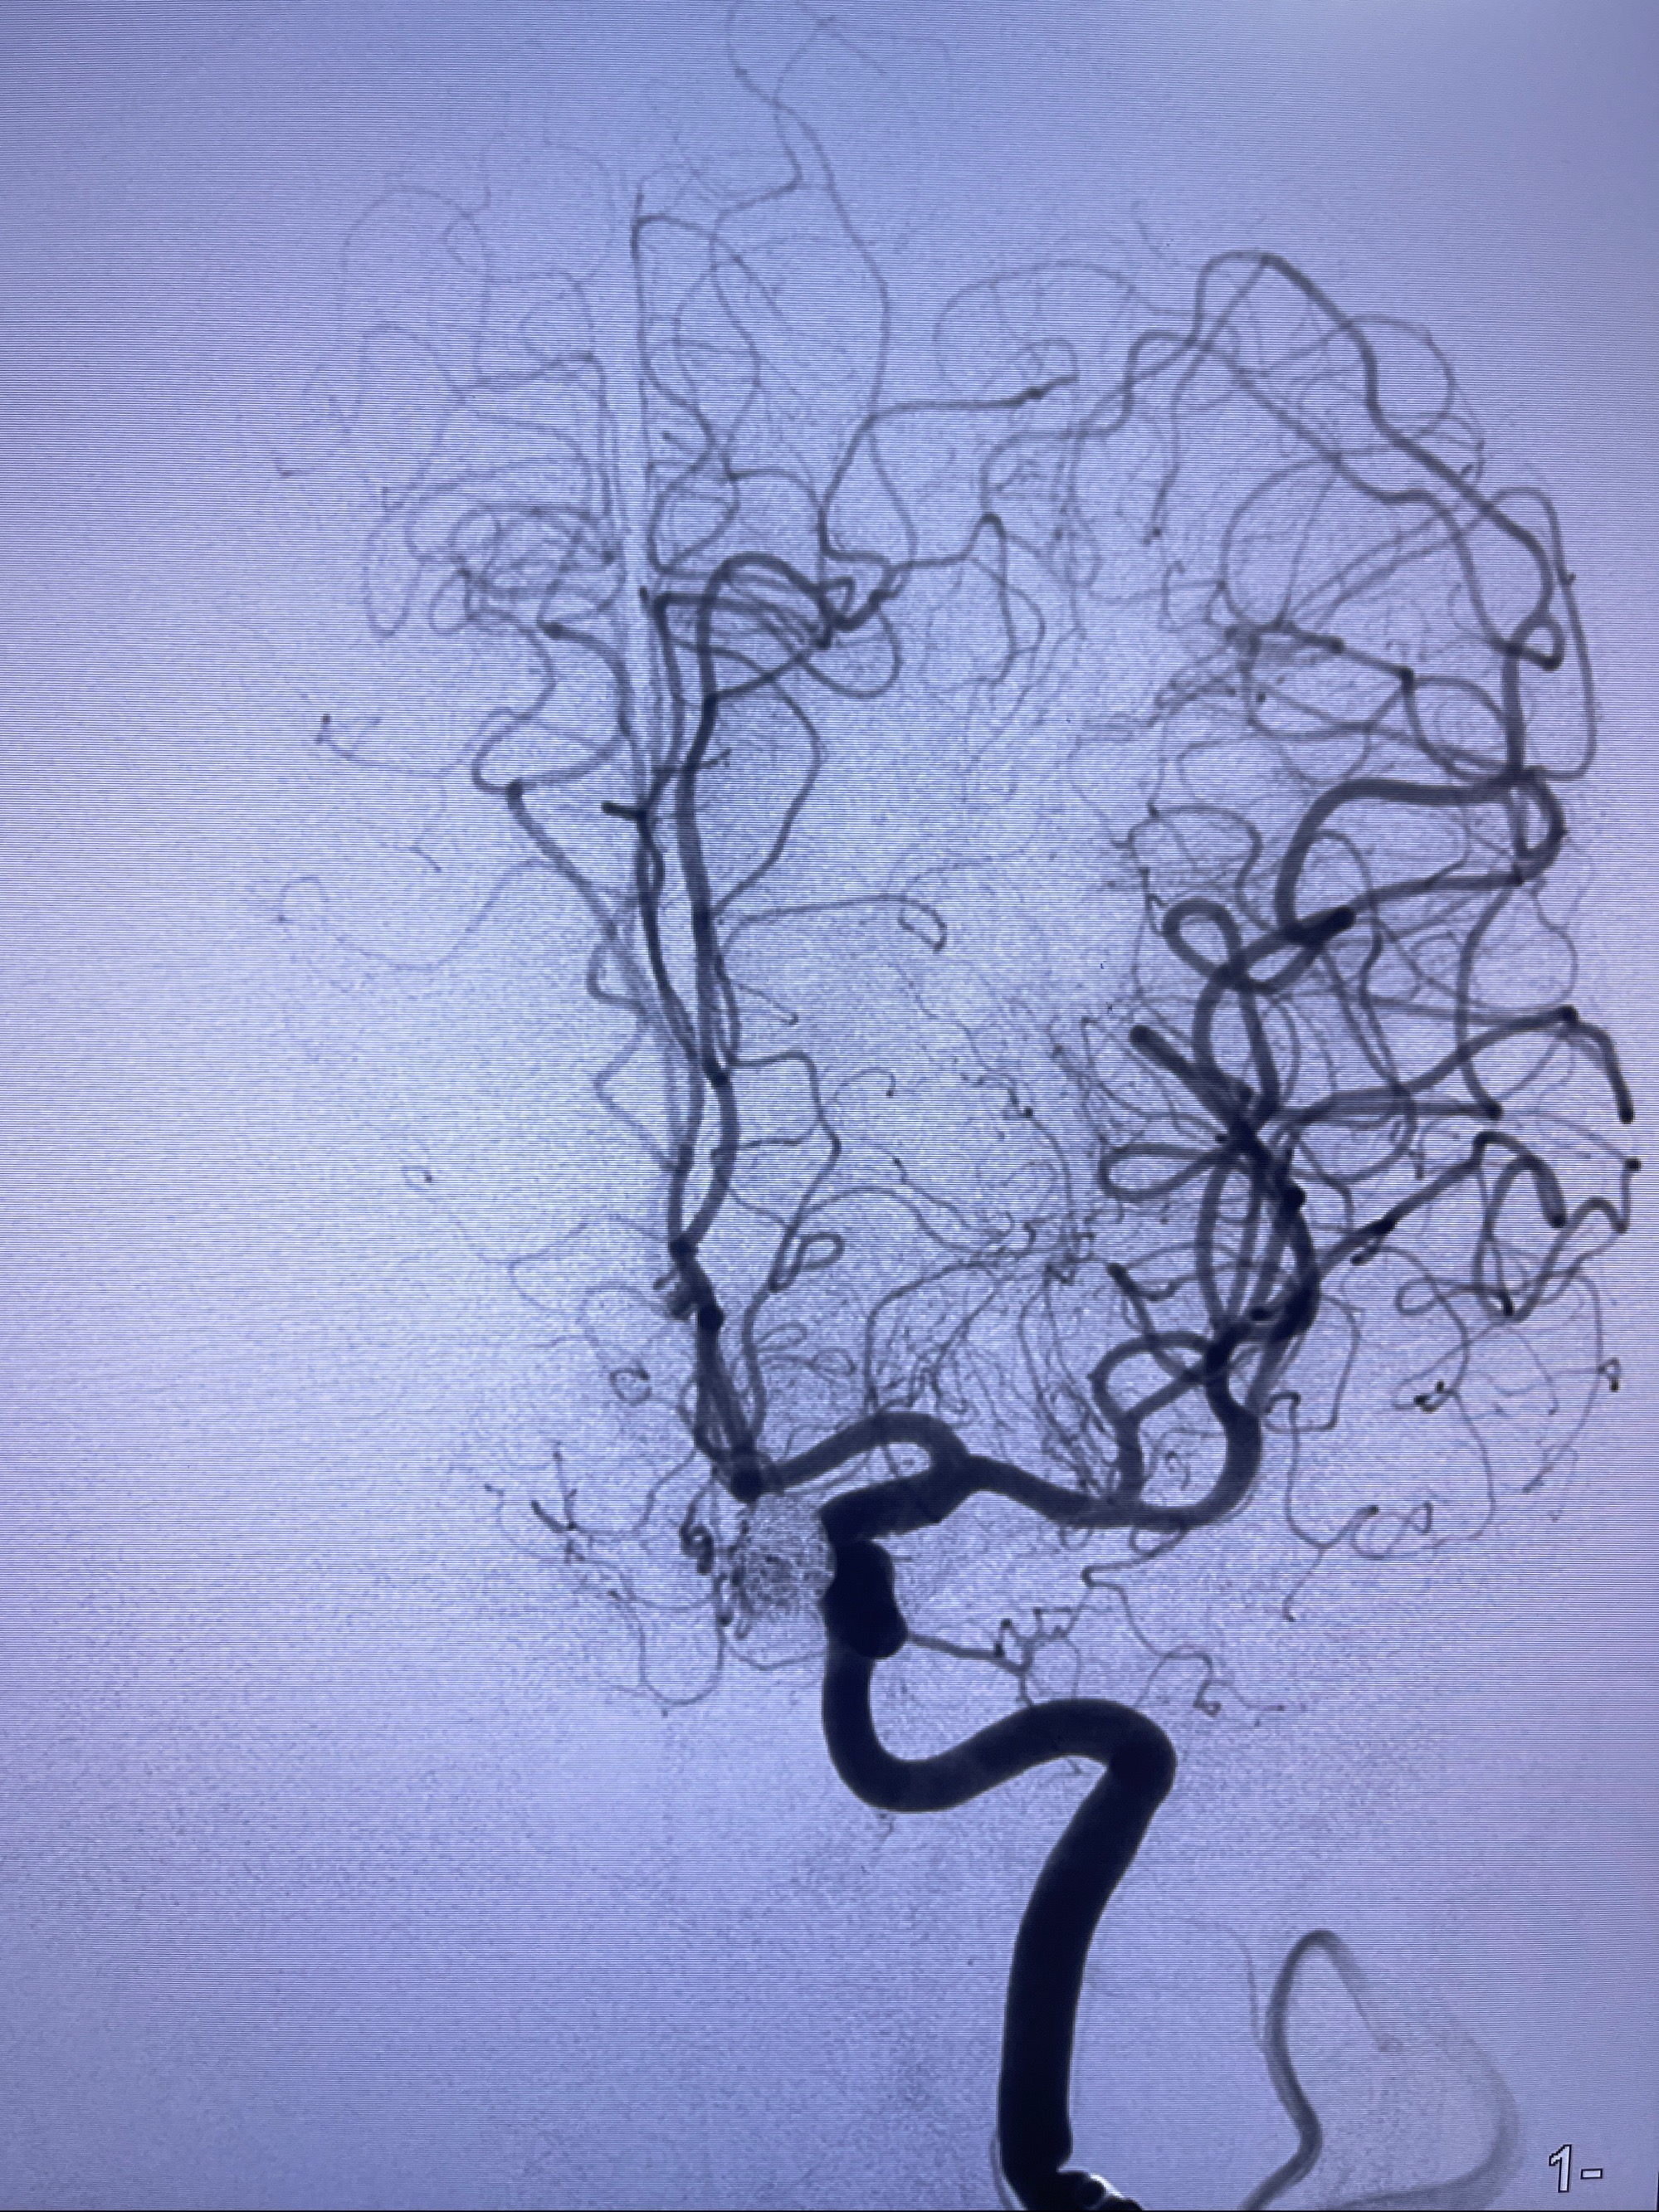

2023-08-30DSA:左侧颈内动脉眼动脉动脉瘤,约3*9.2*7.3mm大小